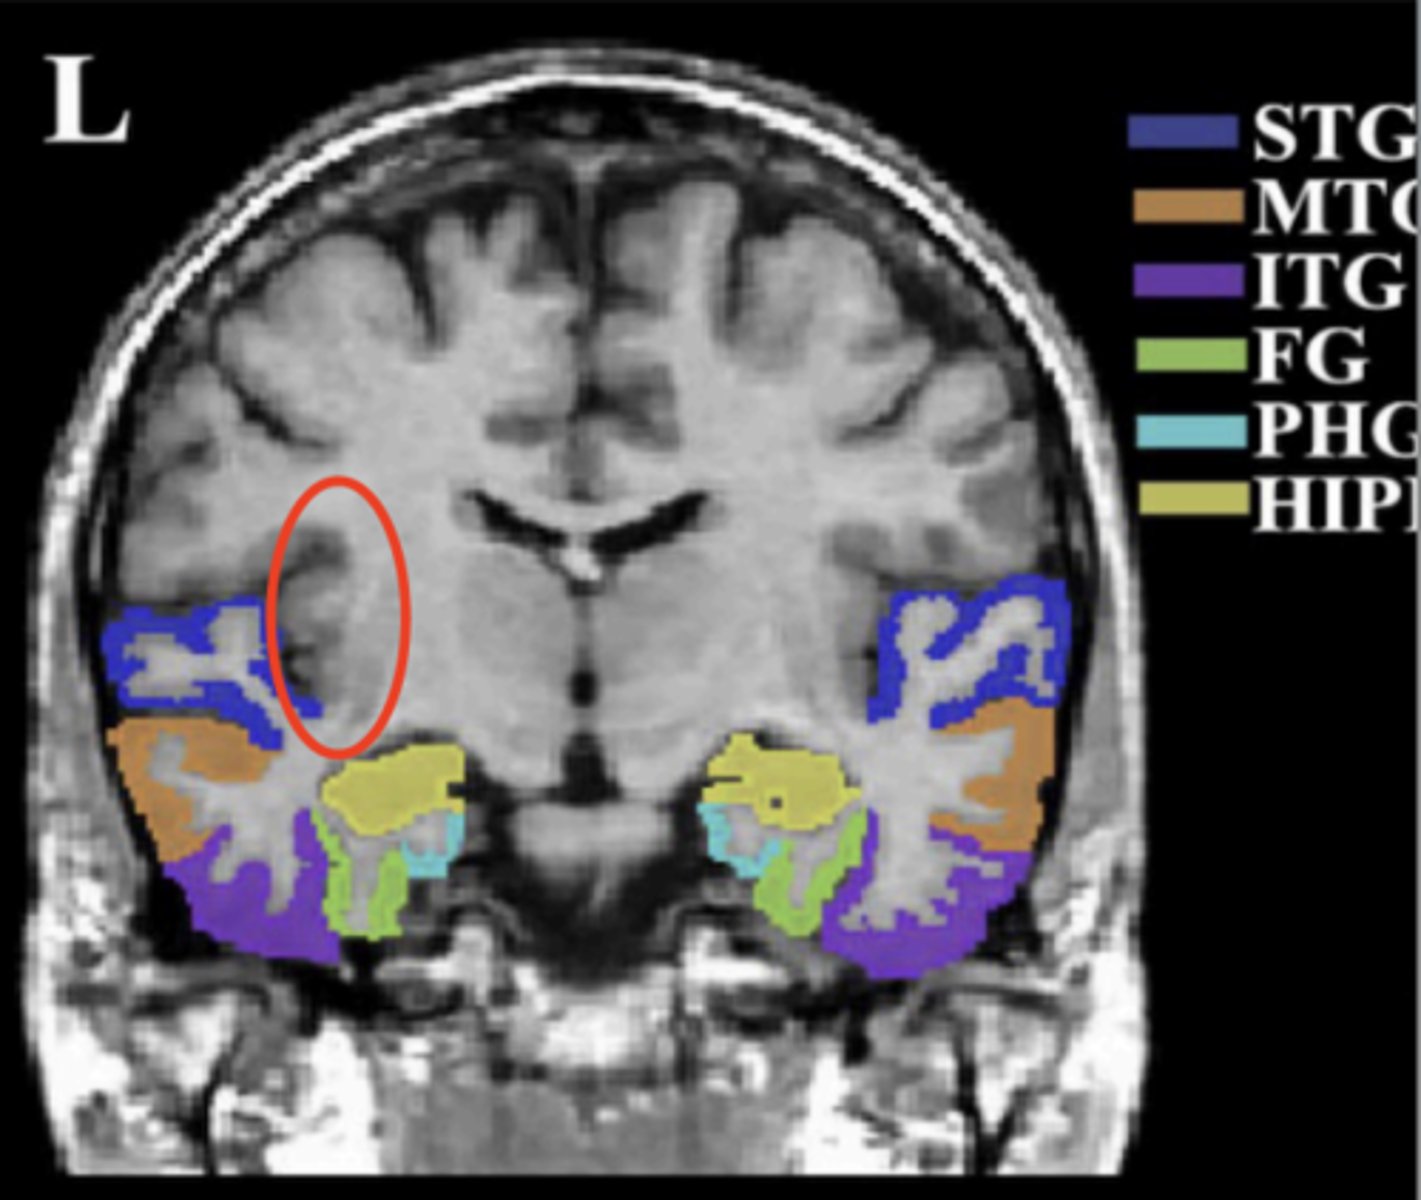

temporal lobe (coronal view)

insula

circled in red, next to STG

superior temporal gyrus (STG)

dark blue area

middle temporal gyrus (MTG)

orange area

inferior temporal gyrus (ITG)

purple area

fusiform gyrus (FG)

green area

parahippocampal gyrus (PHG)

light blue area

hippocampus (HIPP)

yellow area